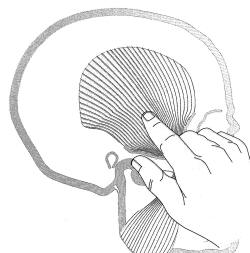

Palpación del músculo temporal |

El temporal también no presenta inconvenientes a la

palpación, dado que es un músculo menos poderoso que el

masetero, solemos pedirle al paciente que apriete sus

dientes co intervalos de descanso, para obtener respuesta

dolorosa a la palpación. |